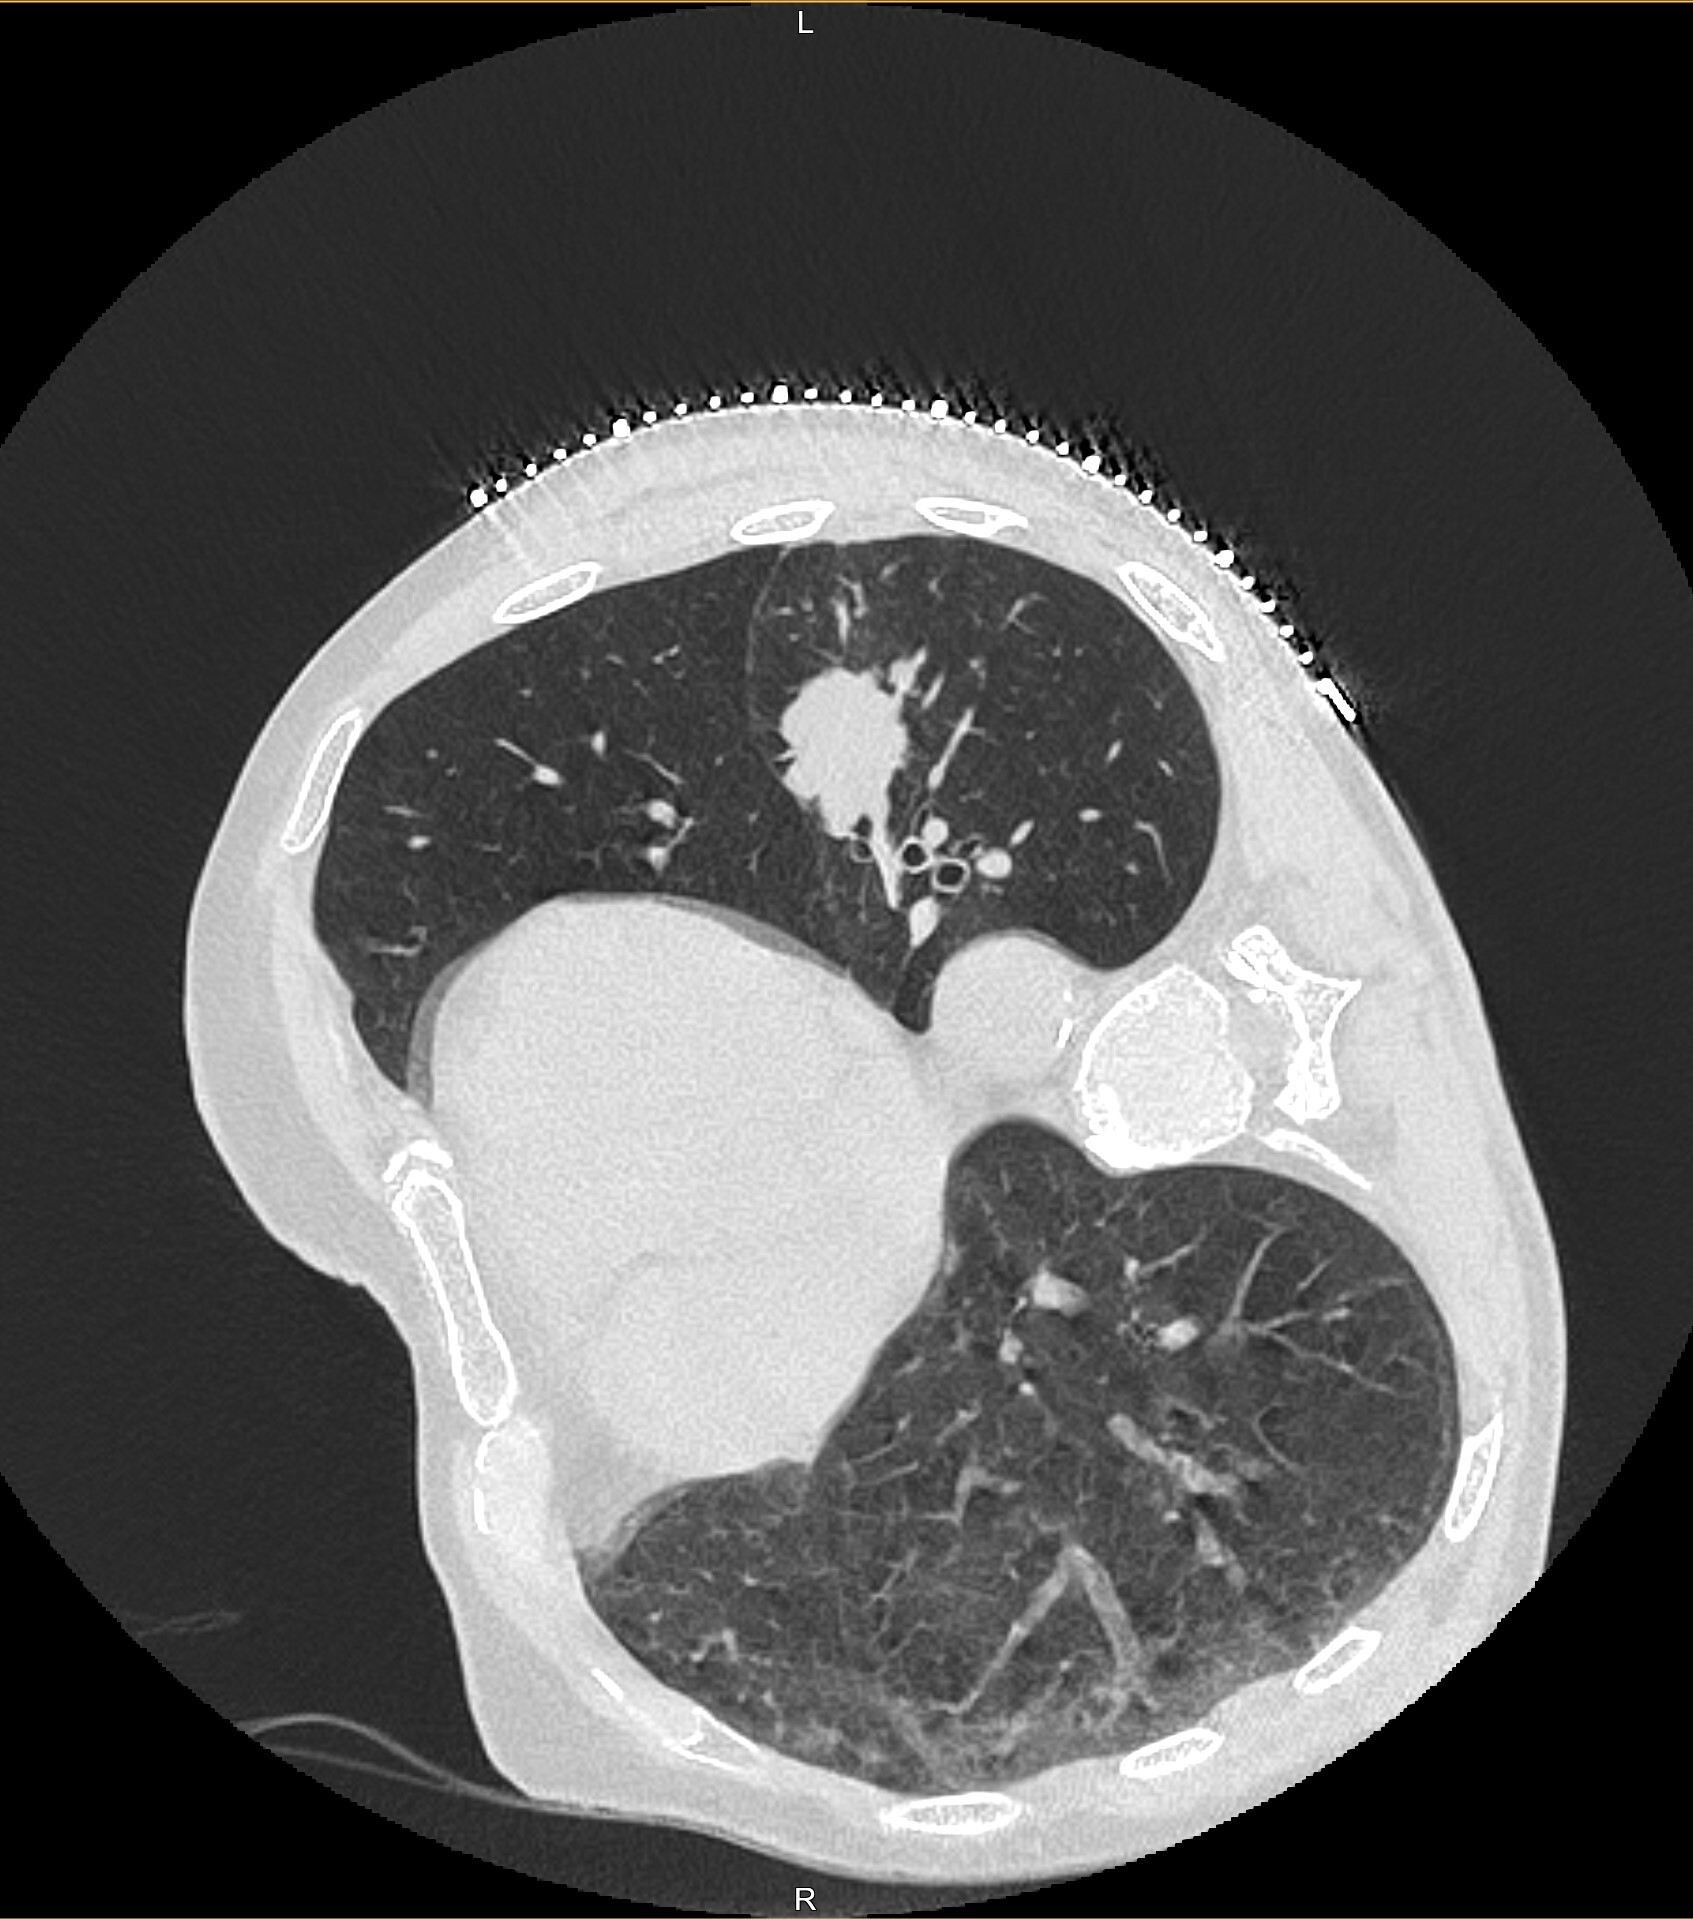

Сегодня мне посчастливилось сделать биопсию лёгкого у мужчины, 68 лет, с подозрением на рак в апикальном сегменте левой нижней доли (на картинках ниже смотрим на правую часть, белое пятно и есть возможное зло). Вроде и образование не шибко маленькое и пункция особых проблем не обещала, но настораживала близость очага к междолевой борозде, которую имелись все шансы повредить, что, статистически, является предпосылкой к пневмотораксу (воздух в плевральной полости):

Но вот контрольный скан после интервенции показал небольшой пневмоторакс (черная область в лёгком):

Беда конечно, но без паники! Он небольшой, так что ещё не всё так плохо. Уложили больного на левый бок, чтобы место пункции было придавлено весом пациента, попросили лежать так 1 час и отправили его в дневной стационар (пункция амбулаторная).